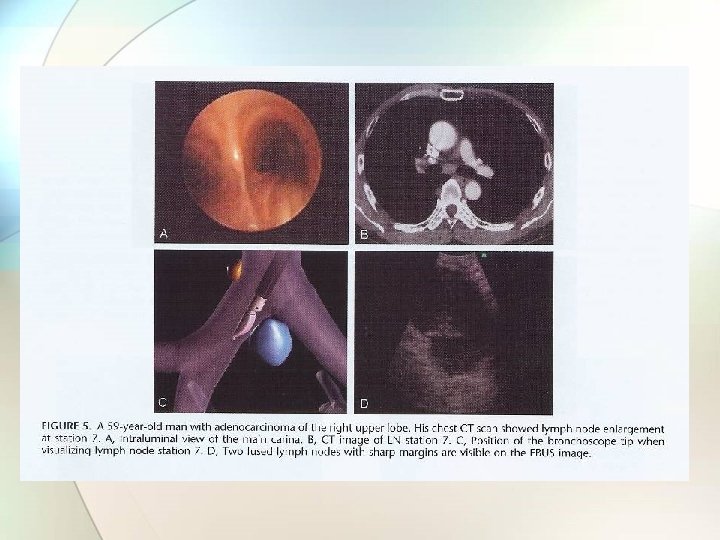

Endobronchial ultrasound (EBUS) • Radial probe (not real-time): for peripheral lesion • Linear probe (real-time): for central lesion − Stations 2, 4, 5, 6, 7 • + doppler function

Image of a transbronchial needle puncture of a small lymph node in the 10 R position Wahidi, M. M. et al. Chest 2007; 131: 261 -274